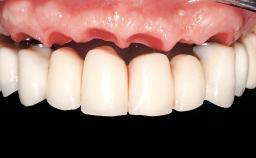

A 63-year-old female patient was referred to the University Medical Center in Groningen, Netherlands, for dental implant treatment. The patient had been edentulous in the upper jaw for 20 years. The remaining teeth in the lower jar had been removed two years before the consultation. The patient was wearing her first maxillary denture and her second mandibular denture; the latter was 1 year old at the time. The conventional upper denture had functioned satisfactorily for many years, but the patient complained about reduced stability and insufficient retention of her lower conventional denture. Her medical history revealed no significant findings. The intraoral examination revealed minor resorption of the maxillary alveolar process and extreme resorption of the mandibular alveolar process.